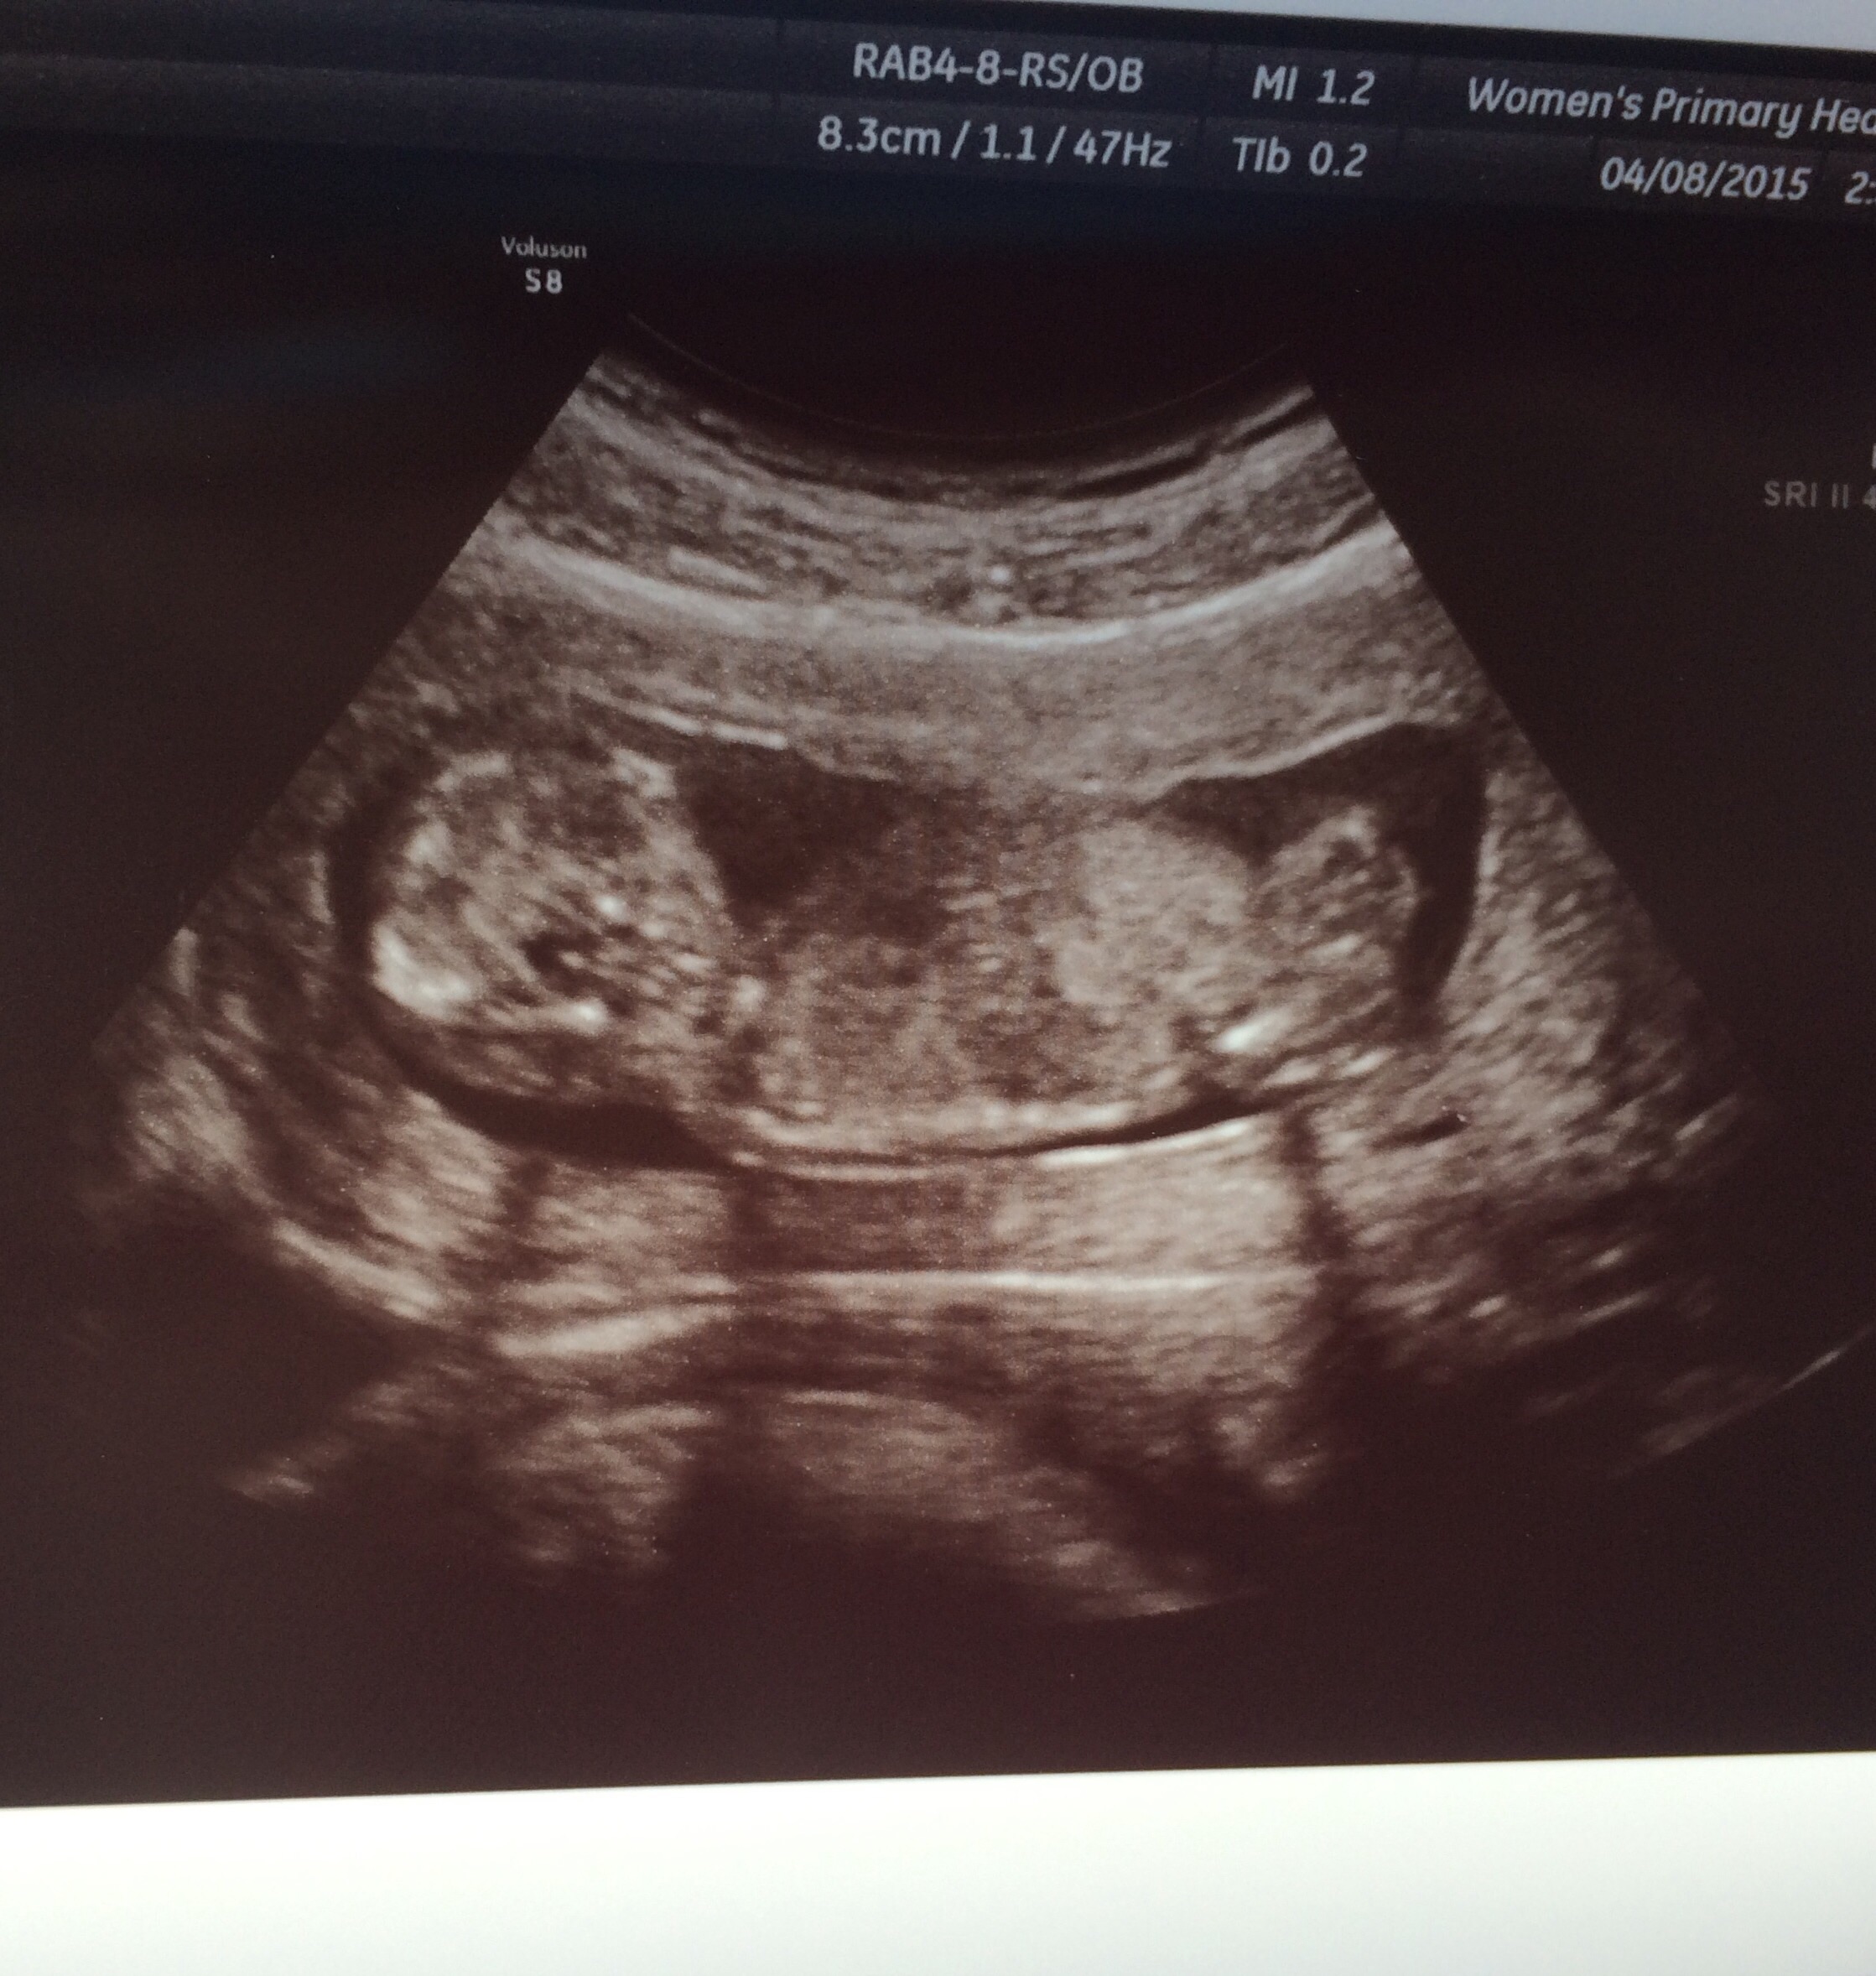

Our little bean at 12 weeks and a few days... Growing real fast now! We were delighted to share the experience with my hubby's sister and our brother in law! The four of us couldn't believe how little bean used all the space and even waved and then rested his/her head behind it's head. Extremely cute! Can't wait to see little bean again soon...

We also graduated up one whole day! 12w 1d today.